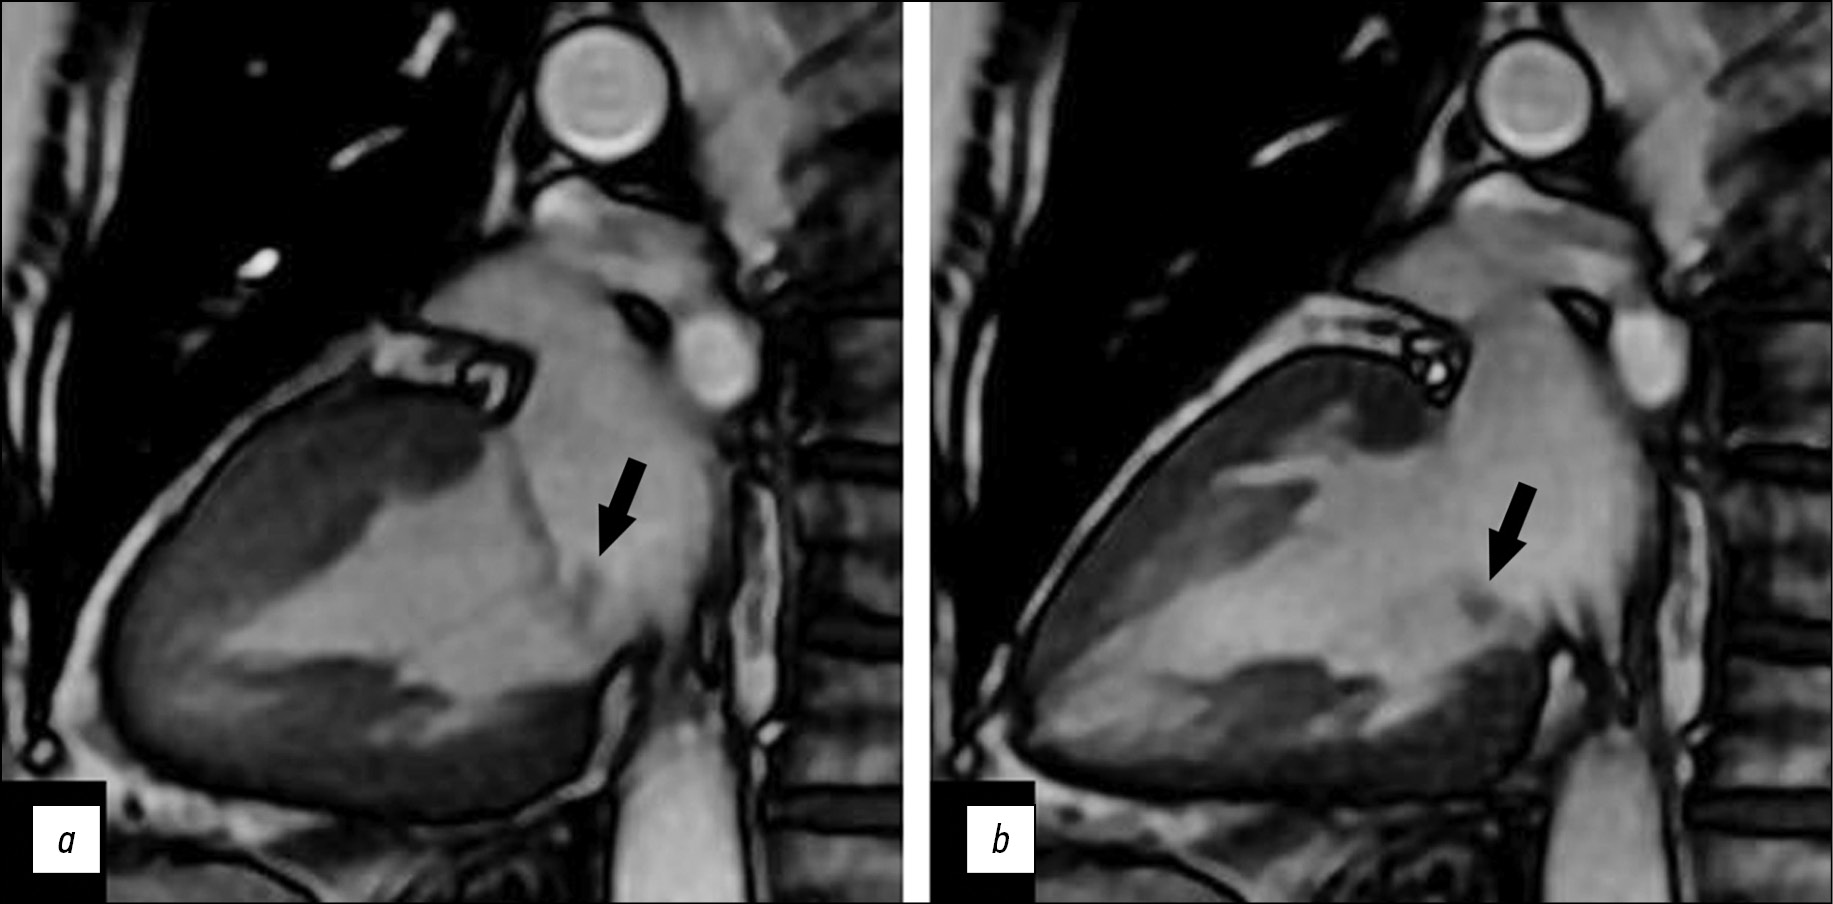

A series of Fiesta-CINE functional examinations in standard axes (two- and four-chamber long axis with 8 mm slice thickness and 0 mm inter-slice interval) was performed after a series of panoramic and axial chest scans in cardiac MRI. Tumor visualization in standard cardiac MRI views was difficult because of the small size of the mass. Optimal mass visualization was obtained in the modified Fiesta-CINE two- and four-chamber views (Fig. 2).

Fig. 2. Magnetic resonance imaging of the heart, two-chamber view: a, left ventricular systolic phase; b, left ventricular diastolic phase. Additional mass on the posterior mitral valve leaflet (black arrows).